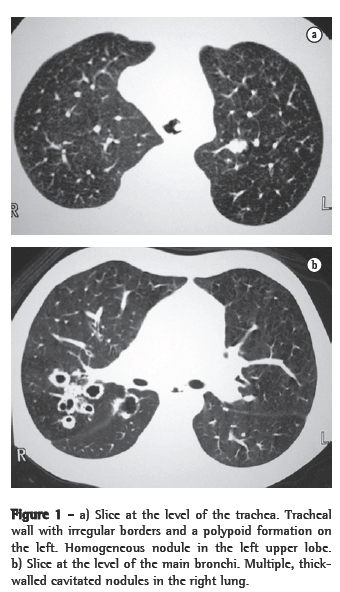

In all eight cases, the CT scans revealed polypoid formations in the trachea. In one case, injury to one of the main bronchi was identified. Seven patients presented involvement of the pulmonary parenchyma. In all eight cases, there were cavitated polypoid lesions, with irregular internal borders and walls of various thicknesses, multilobulated in six cases and presenting confluence of the lesions in five (Figures 1 through 5). Solid nodules were seen in six patients. An air-fluid level was observed in only one patient. The lesions were predominantly in the lung bases in three patients and in the middle thirds in two, whereas they were evenly distributed in two. In one patient, the lesions were accompanied by a mass, and, in another patient, they were accompanied by consolidation. In the latter case (Figure 5), there was malignant degeneration in multiple lesions. Signs of air trapping were also observed in one case. There were no identified instances of lymph node enlargement or pleural effusion.

Chest X-rays are inferior to CT scans of the chest, especially those performed using spiral CT (volumetric acquisition), in the initial phases of pulmonary dissemination, due to the fact that CT better characterizes and allows better visualization of nodular tracheobronchial vegetation, Tomographic findings include focal or diffuse airway narrowing caused by the nodules. The nodules form on the mucosal surface, and their invasion into the lumen is best evaluated using CT.(3) These alterations are easily correlated with the disease when there is a clinical history of papillomatosis.(4) Other findings related to airway obstruction and accompanying infections are atelectasis, consolidations, air trapping and bronchiectasis.(2-4) In our sample, polypoid formations in the trachea were observed on all of the CT scans Seven patients presented involvement of the pulmonary parenchyma, characterized by cavitated polypoid lesions with irregular internal borders and walls of various thicknesses, with a multilobulated aspect and a tendency toward confluence. Solid nodules were seen in six patients. None of the patients presented lymph node enlargement or pleural effusion.